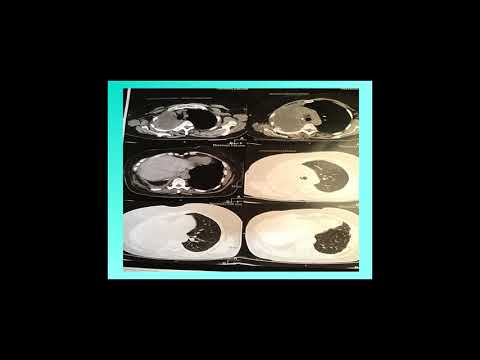

Caso Clinico presentado por la Dr Judith Sappag

Caso Clìnico Presentado por la Dra Vanina Martin

Caso Clínico presentado por la Dra Lilian Capone

Caso Clínico presentado por Dr Adrián Gasse

Caso Clínico presentado por Dra Vanina Martín

Caso Clínico Rol de las drogas antifibróticas en la patología intersticial ocupacional Dra Silvia Qu

Caso Clinico Nanomateriales y Fibrosis Pulmonar - Dra Vanina Martin

Caso Clinico Dra Balbi Brenda